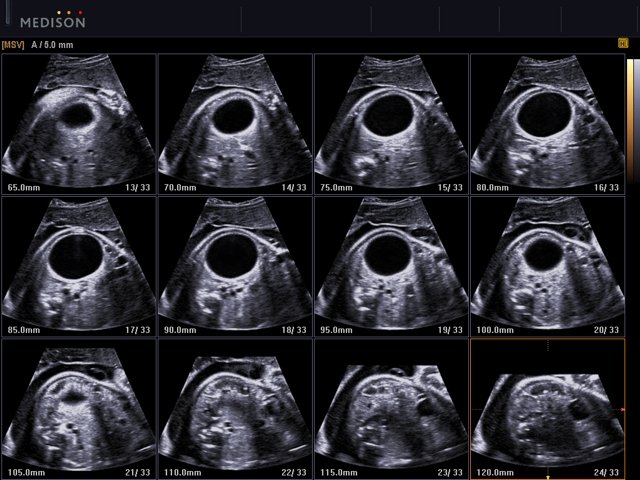

- MSV (Multi-Slice View или мультислайсинг) - возможность одновременного просмотра на экране множественных срезов, полученных при трехмерном сканировании.

- VolumeCT - трехмерная реконструкция изображений в виде куба (Cube Sectional View) или трех пересекающихся плоскостей (Cross View).